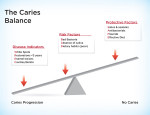

Perhaps the most important model that has been developed is the Featherstone Caries Etiology model (2007).7 This model (Figure 6) illustrates that disease control is dependent on a delicate balance between the protective commensals of the oral cavity and the risk factors present in the patient. This teeter-totter model simply explains that if there is an imbalance in the system that enables risk factors to outweigh protective factors, disease is the final outcome. If these risk factors are long term, then the caries process can and will run rampant and eventually destroy the dentition (Figure 7 and Figure 8). A Caries Sequence Model (Figure 9) has been adapted by Brian Nový, DDS, assistant professor of Restorative Dentistry at Loma Linda University. In this model, Nový states that low intraoral pH is the main ingredient in the overall sequence, confirming the adage, “If you don’t address the pH problem, you cannot control the disease.”